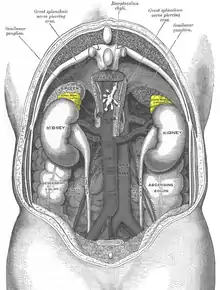

Structure of norepinephrine

Structure of norepinephrine- More likely to indicate an extra-adrenal tumor[74]

- Patients are more likely to present with continuous, persistent pheochromocytoma-related symptoms (hypertension and tachycardia) compared to those that are classically episode with an adrenergic phenotype[62]

- Common in patients with von-Hippel Lindau and succinate dehydrogenase subunit X genetic variants[62]